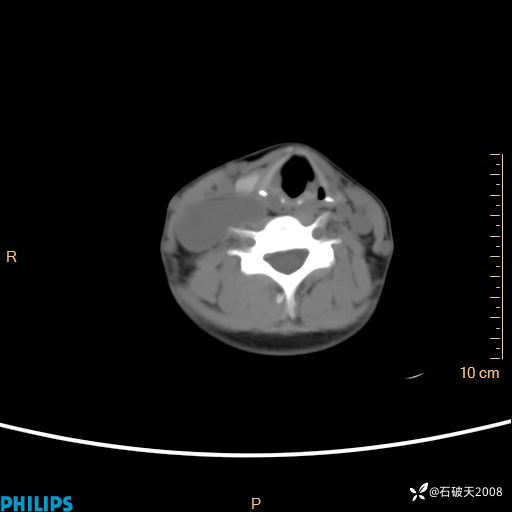

动脉期